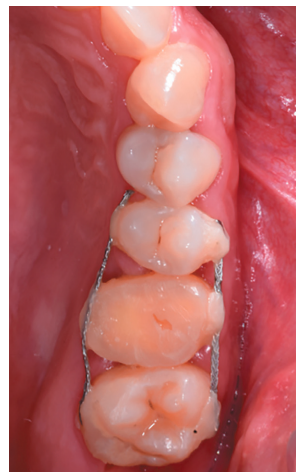

A los diez días se retiró la sutura, donde se apreció una buena cicatrización de los tejidos blandos (Figura 15). A las tres semanas del postoperatorio se procedió al tratamiento de conductos, observándose una correcta evolución (Figura 16).

Transcurridos 2 meses se realizó una nueva revisión clínica (Figura 17) y radiográfica mediante radiografía periapical (Figura 18), procediéndose a retirar la ferulización. A los 3 meses se realizó otra revisión clínica (Figura 19) y radiográfica mediante radiografía periapical paralelizada (Figura 20), donde se puede observar una adecuada formación ósea alrededor del diente trasplantado.